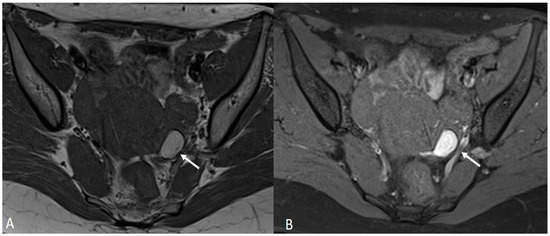

In order to perform a correct evaluation, the bladder must be at a degree of repletion suitable for the correct study of its walls and its lumen: those nodules or masses are responsible for the loss of the normal hypointense signal of the muscularis layer on T2WI. Hemorrhagic content may also be seen as hyperintense foci on T1WI, and it is also possible to observe hyperintense cystic areas on T2WI [7,14] (Figure 1).

Figure 1.

Localization of endometriosis in the vesico-uterine pouch in a 42-year-old female. (A) Sagittal T2WI (black arrow); (B) Sagittal fat-suppressed T1WI (white arrow); (C) Coronal T2WI (black arrow).

In the case of a mural mass protruding into the lumen, mucosal or submucosal edema is well depicted on T2WI [40].